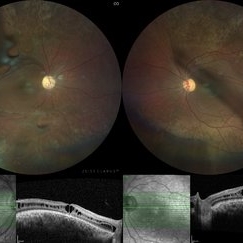

Juvenile X-Linked Retinoschisis

Fundus Photograph of a 25-year-old male with juvenile x-linked retinoschisis with inner retinal defects seen above superior and inferior arcades in both eyes. Corresponding OCT showing retinal schisis involving fovea.

Photographer: Shishir Verghese, Aravind Eye Hospital and Postgraduate institute of Ophthalmology, Coimbatore

Imaging device: Zeiss Clarus

Condition/keywords: juvenile retinoschisis, retinoschisis